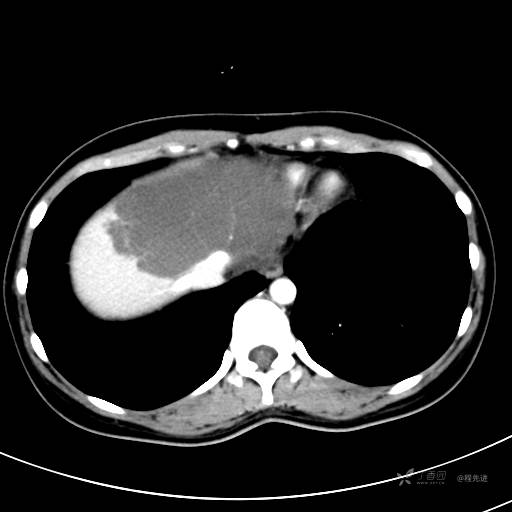

CT平扫+增强,每个序列3张图

CT值 平扫48HU 动脉期66HU 静脉期68HU 延迟期62HU